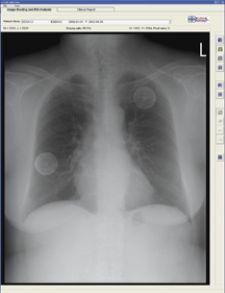

Riverain’s OnGuard chest X-ray computer-aided detection (CAD) software helps identify nodules that may be early-stage ...

April 20, 2011 – A new study published in Radiology has demonstrated that using a bone suppression application with ...

Lung cancer is the most common form of cancer found today. There are two primary types - small cell and nonsmall cell ...